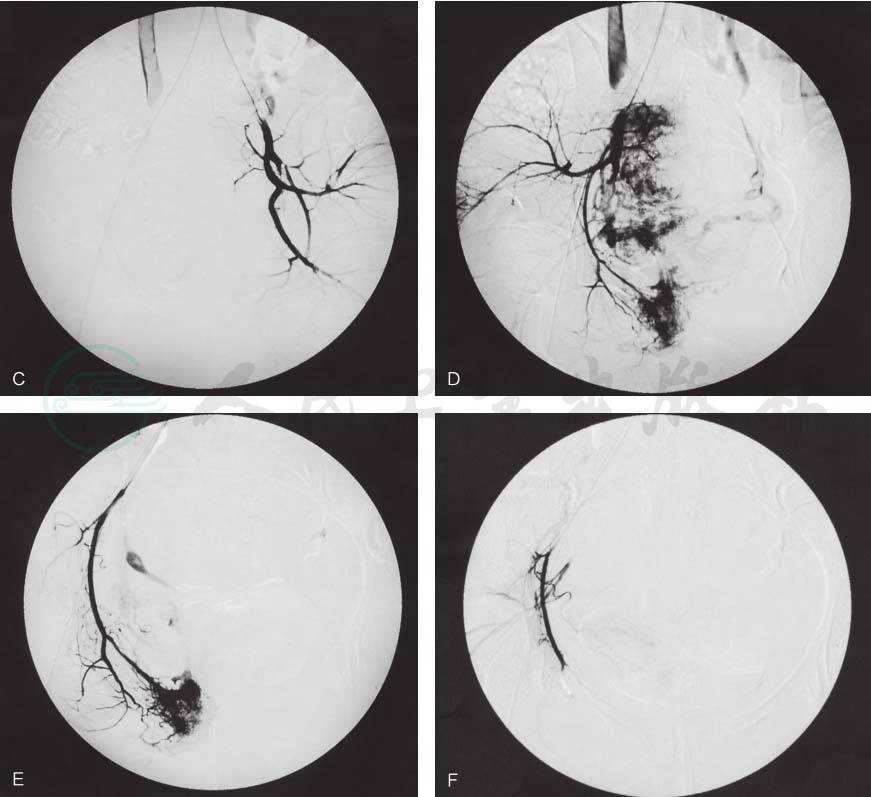

对于盆腔病变较严重且转移瘤较大的破裂出血患者,阴道填塞联合化疗,有时也难以有效控制出血。自1972年Rosch等首先应用选择性动脉栓塞术治疗急性消化道出血获得成功以来,该项技术已越来越多地应用于治疗急性、危重的出血患者,包括腹腔内出血、腹膜后出血等。动脉造影能很快明确出血部位,选择性动脉栓塞术可以准确阻断出血部位的血供,及时止血。Method等报道了一例侵蚀性葡萄胎阴道转移(4cm×5cm)患者于化疗1疗程后发生破溃大出血,他们以明胶海绵栓塞了右髂内动脉发出的三个分支,从而控制了阴道出血。浙江省金华市中心医院报道了13例妊娠滋养细胞肿瘤阴道转移的患者中有3例大出血患者因填塞效果差行选择性动脉栓塞术及全身静脉化疗后疾病缓解,定期随访(最长达8年)均无复发。北京协和医院曾对3例阴道转移大出血患者反复阴道填塞结合化疗仍未能控制出血后,行盆腔动脉栓塞术,出血均得到有效控制,栓塞后不再需要阴道填塞(图2)。可见,对于较凶险的转移灶破溃出血及时采用动脉栓塞可明显降低阴道填塞的次数,减少患者失血量,避免多次输血和感染的发生。但是,对于较严重的阴道穹窿和宫颈病灶,有时单纯通过子宫动脉栓塞并不能取得很好的止血效果,还是需要同时进行阴道填塞术。笔者诊治过这样的一例患者:杨××,21岁,2007年2月28日因“胚胎停育”清宫后血β-HCG>200 000mIU/ml,肺CT示双肺多发转移瘤、盆腔超声示宫颈下段及阴道穹窿处可见8.8cm×6.2cm×4.1cm不规则低回声、盆腔查体示阴道右前壁6cm紫蓝色肿物,已破溃,出血不止,而行双侧子宫动脉栓塞术,同时给予(VCR+5-FU+KSM)化疗。栓塞后仍有阴道出血,血红蛋白最低50g/L,于2007年3月4日行阴道填塞,见右前穹窿至阴道上1/3呈破溃凹陷状,出血汹涌,每2天更换填塞一次,辅以云南白药等,至第5次时,出血基本局限,予以缝扎,第6次填塞于2007年3月15日取出后,出血基本止住。2007年3月20日后阴道基本不再出血。化疗3疗程后血β-HCG降为正常,末次化疗时间2007年7月28日,患者至今无病存活。

图2患者的造影表现

A:盆腔及阴道转移瘤出血盆腔动脉造影所见;B:左侧髂内动脉造影所见;C:左侧子宫动脉及阴部内动脉栓塞术后;D:右侧髂内动脉造影所见;E:右侧阴道动脉造影见有造影剂溢出;F:右侧阴道动脉栓塞术后;G:右侧子宫动脉造影所见并置管化疗

引自:宋鸿钊滋养细胞肿瘤学(第4版).第4版.ISBN:978-7-117-30225-8.主编: